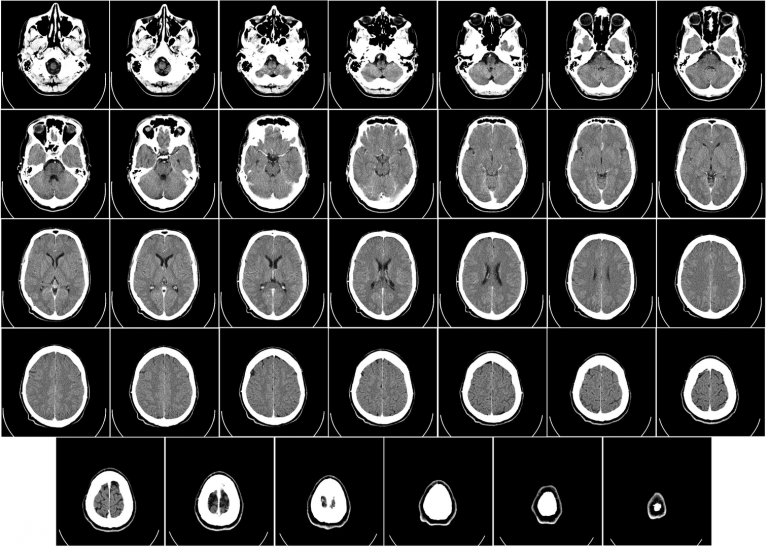

Image: CT scan of a human brain (nothing strange was found). Image credit: Department of Radiology, Uppsala University Hospital. Uploaded by...